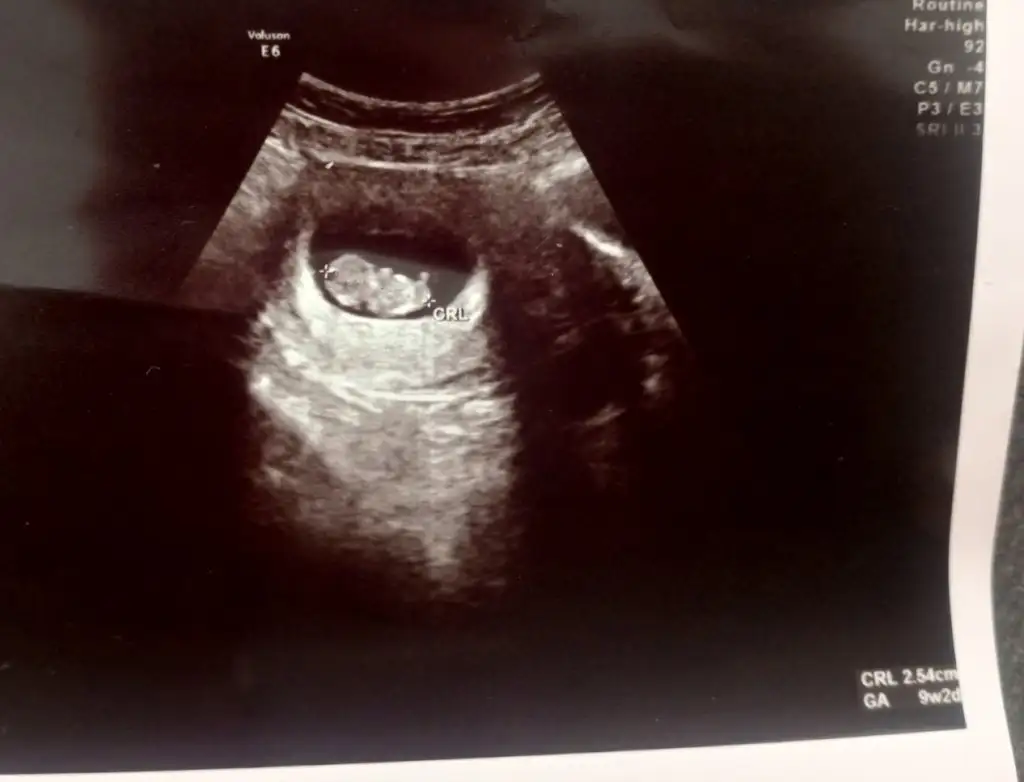

Kız benimki vajinal ultrason attığımKarından ultrason da ayna görüntüsü olarak düşünüyor sun. Yani sağ da se aslında solda ben öyle biliyorum

Seninki de kıza benziyor. Önceki hamileliğim benimde aynı tarafta idi seninki ile. Karın ultrason la yine. Bilen arkadaşlar Kız demişti. Şimdi benimki solda yani aynalar sak sağdaBuda benim ki

Vajinal ultrason vallaKarından ultrason ise kıza benziyor

Benimki mi erkeğe benziyorKızlar karından ultrason. Ramse teorisine göre erkek görünüyor bakalım tutacak mı sizde atın tahmin edelim